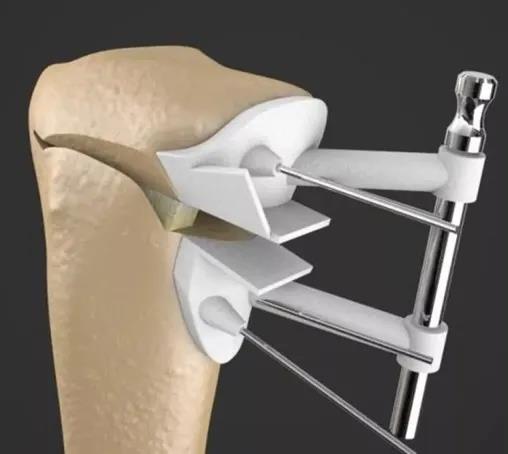

Hippocrates 及其弟子采用徒手或机械整复骨折,木质夹板固定整复后骨折的位置。

四肢骨折、关节脱位手法复位夹板外固定

肩关节脱位的手牵足蹬复位法;